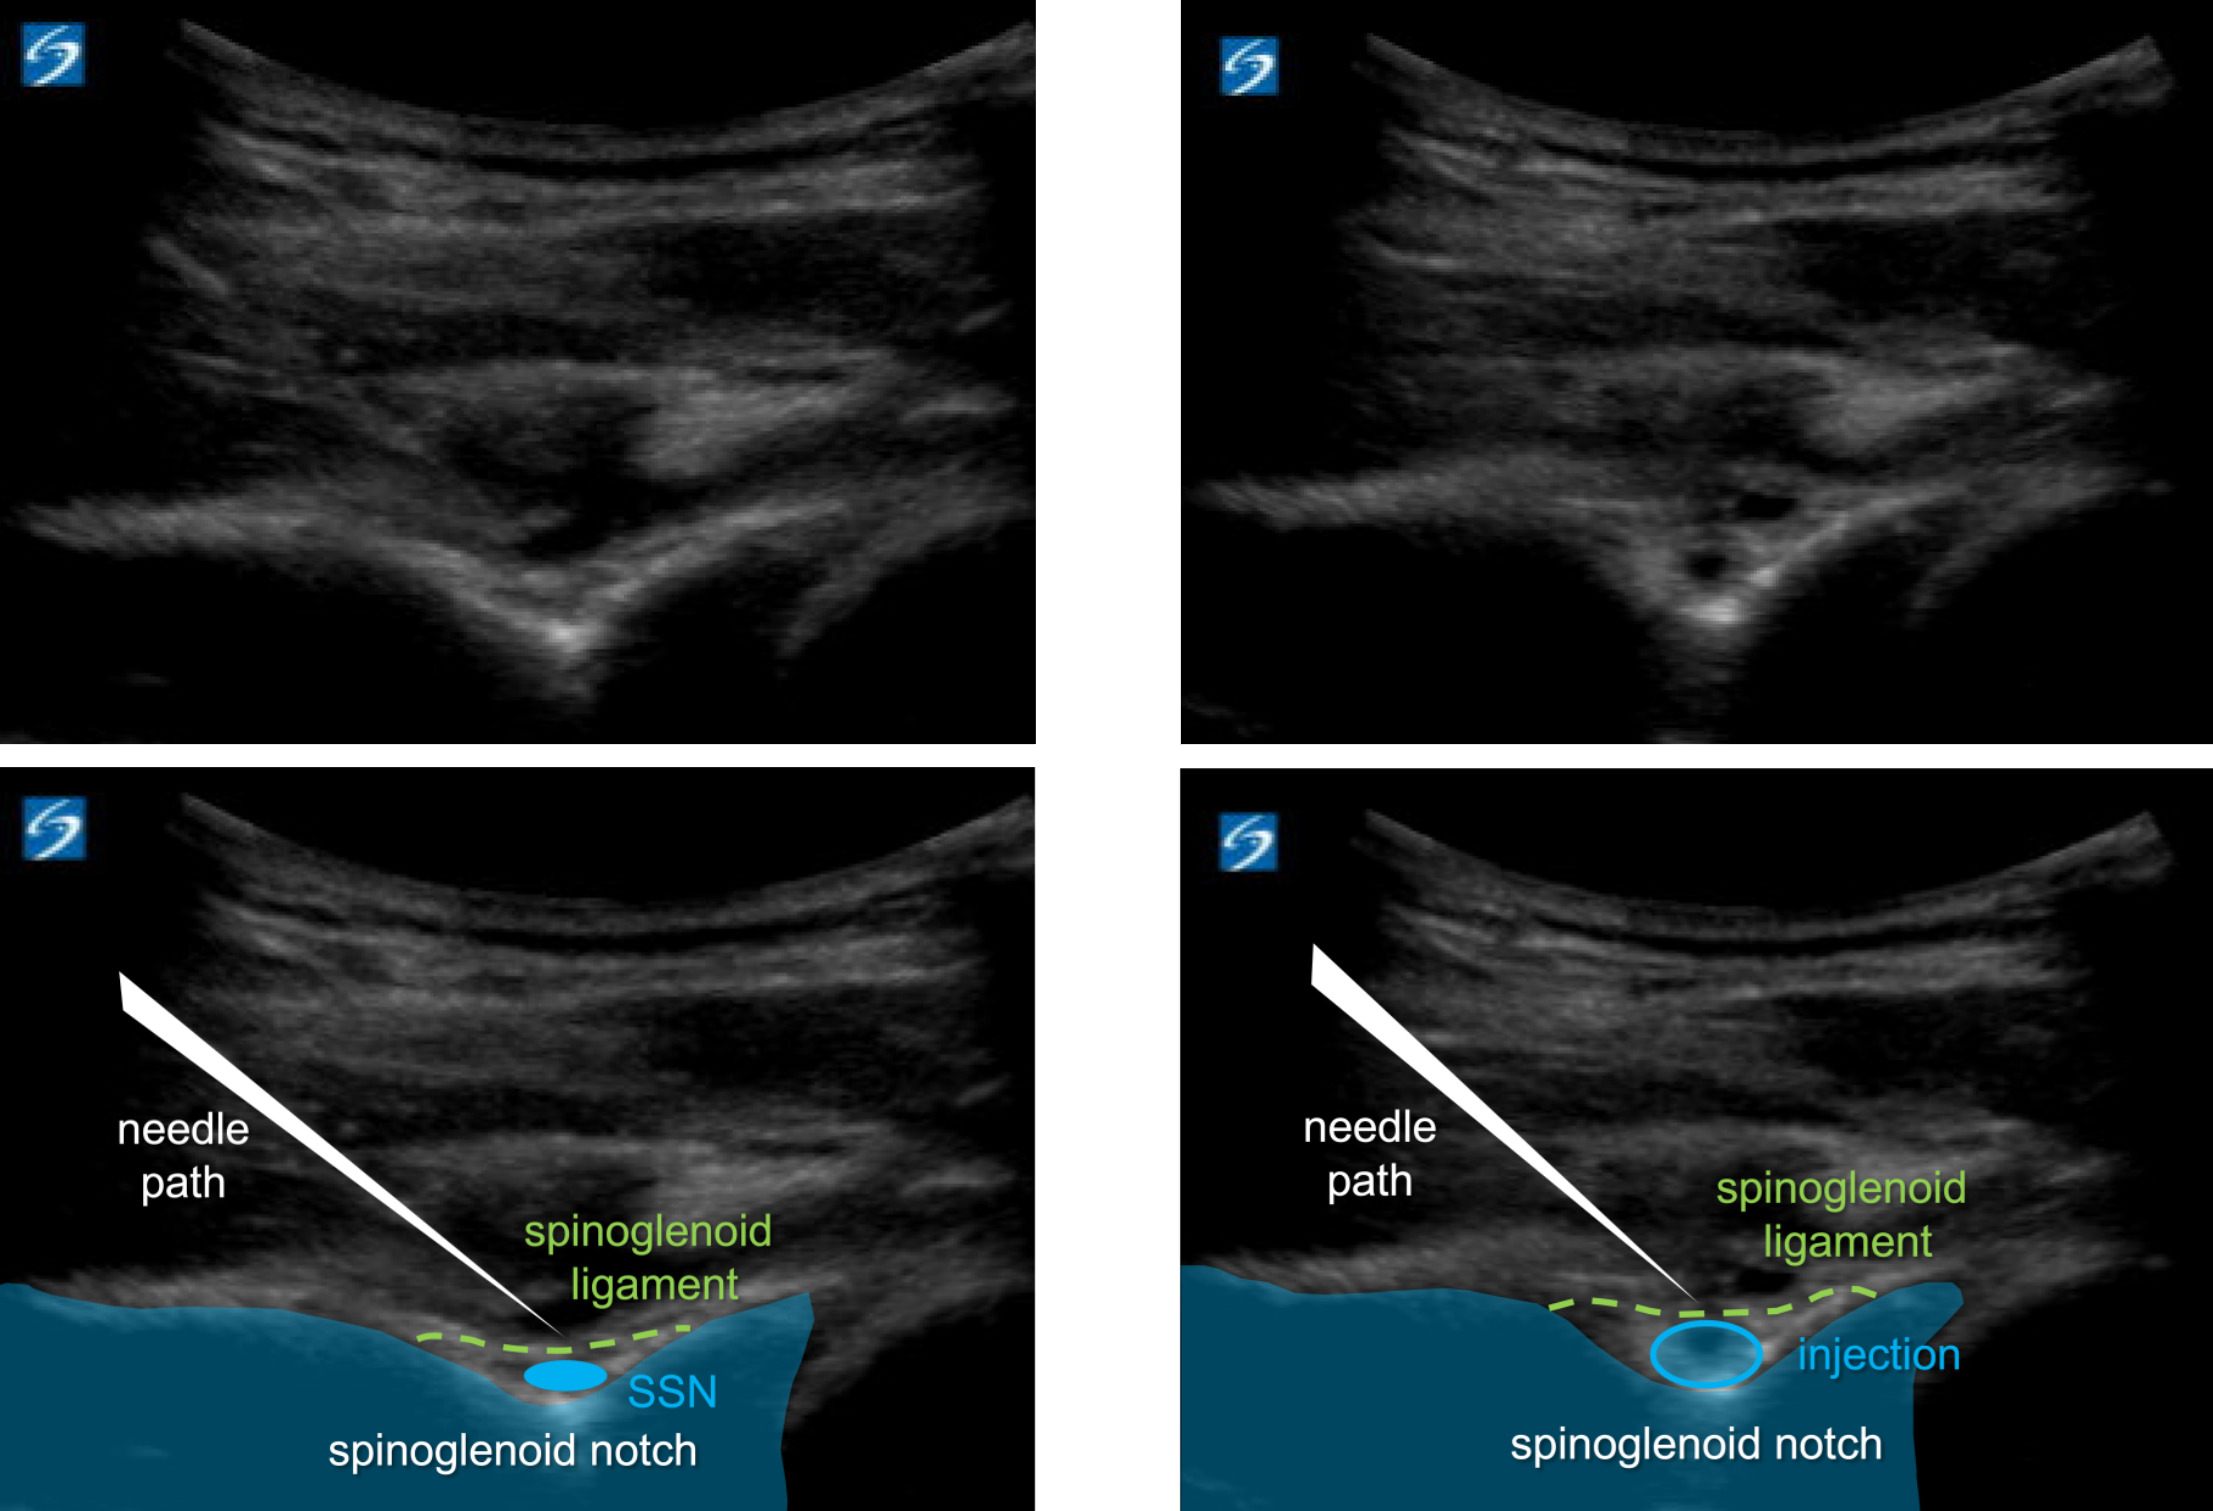

First, a suprascapular nerve injection either at the suprascapular notch or at the spinoglenoid notch is performed. This nerve block allows the patient to better tolerate the large volume second injection as well as the post-procedural manual stretching. Typically, a posterior musculoskeletal ultrasound (MSK-US) approach is utilized (Figure 1) to inject 3-5 cc of 1% lidocaine under the transverse ligament surrounding the notch.